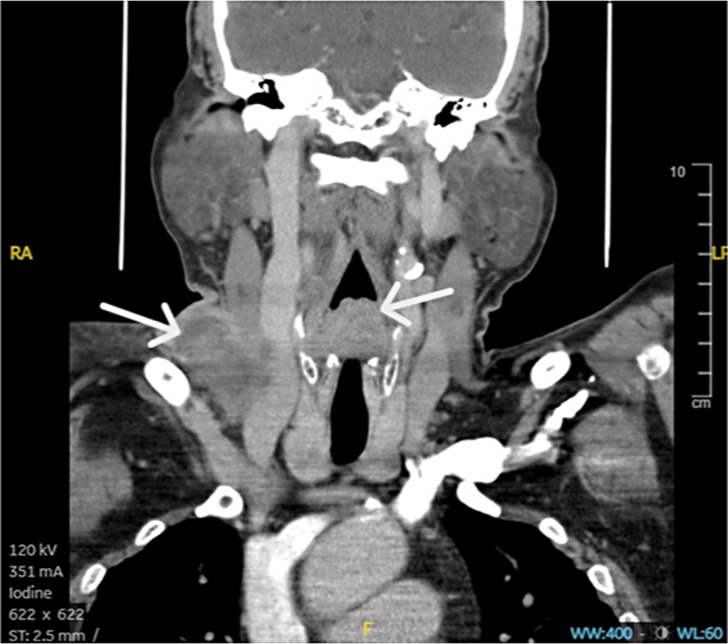

Case presentation: We present a case of a locally advanced hypopharyngeal squamous cell carcinoma in a 63-year-old Arabic man who was started on pembrolizumab, docetaxel, and cisplatin for the first treatment cycle, but he failed to show up for the subsequent cycles due to the coronavirus disease 2019 pandemic restrictions. He came back after 10 months with complete clinical and radiological response.

Conclusion: The present report may possibly be the first to report a case of locally advanced squamous cell carcinoma of the hypopharynx that showed complete clinical and radiological response to a single dose of pembrolizumab, docetaxel, and cisplatin.